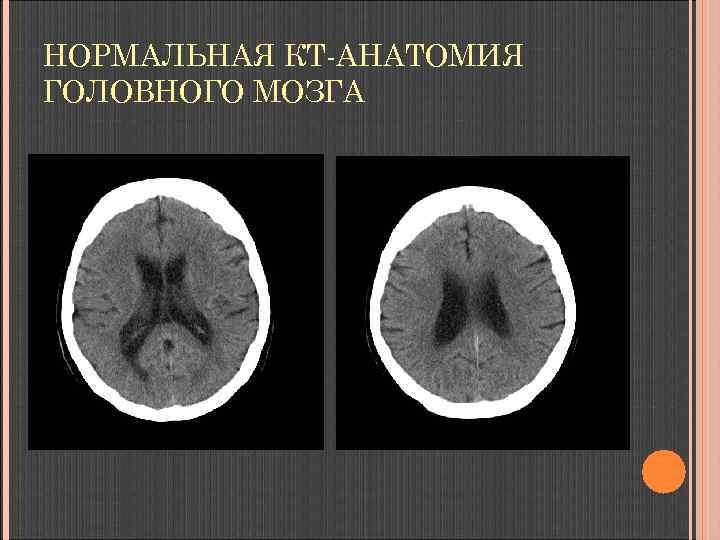

НОРМАЛЬНАЯ КТ-АНАТОМИЯ ГОЛОВНОГО МОЗГА Неизмененные ткани мозга: серое вещество 36 -40 ед. НU, белое вещество 24 -36 ед. НU

НОРМАЛЬНАЯ КТ-АНАТОМИЯ ГОЛОВНОГО МОЗГА